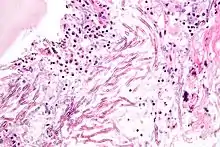

Аспергиллёз

Аспергиллёз — группа заболеваний, вызываемых грибами рода аспергилл. Наиболее распространённый подтип инфекций придаточных пазух носа, ассоциируемый с аспергиллёзом, вызывается видом A. fumigatus[22]. Симптомы включают жар, кашель, боль в груди или диспноэ (одышку), что также проявляется и в случае многих других заболеваний и поэтому может усложнить диагностику. Обычно восприимчивы только пациенты с уже ослабленной иммунной системой или страдающие от других болезненных лёгочных состояний. Главными формами заболевания у человека являются[23][24]:

- Аллергический бронхолёгочный аспергиллёз, поражающий больных с респираторными инфекциями, такими, как бронхиальная астма, муковисцидоз (кистозный фиброз), и синусит

- Острый инвазивный аспергиллёз — форма аспергиллёза, при которой грибки прорастают в окружающие ткани, более часто случается у людей с ослабленной иммунной системой, например на фоне СПИДа или обусловленной курсом химиотерапии

- Рассеянный инвазивный аспергиллёз — инфекция, широко распространившаяся в организме

- Аспергиллома — шаровидное грибковое образование, которое может сформироваться в пазухах и полостях, например, в лёгких

Чаще всего грибок проникает внутрь через дыхательные пути и рот и может поражать как дыхательную систему, так и центральную нервную систему, пищеварительный тракт, кожу, органы чувств и половую систему. Аспергиллёзный менингит или энцефалит в большинстве случаев заканчивается летальным исходом. Встречаются также грибковые поражения селезёнки, почек и костей аспергиллами, однако большей частью они вызваны вторичной инфекцией. Аспергиллёз дыхательных путей часто диагностируют у птиц, и известны определённые виды аспергилл, заражающие насекомых[4].